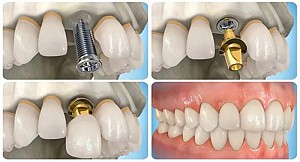

Hiện nay, kỹ thuật cấy ghép implant là một kỹ thuật giúp phục hồi chiếc răng bị mất một cách hoàn hảo, với kỹ thuật tiên tiến hiện đại bậc nhất hiện nay. Được nhiều người dân Việt Nam biết đến và đã, đang, sẽ sử dụng phương pháp này trong trường hợp mất răng. Nguyên tắc của phương pháp này là cấy chân răng giả vào xương hàm của bệnh nhân bị mất răng. Rồi sau đó một thời gian khi chân răng dính vào xương hàm thì nha sĩ sẽ chụp phần răng sứ lên trên vừa khít với khoảng trống răng mất, vừa đảm bảo khả năng ăn nhai và hiệu quả thẩm mỹ.

Các chân răng implant được cố định một cách chắc chắn trong xương hàm nhờ quá trình trụ được tích hợp với xương. Nhờ vậy mà răng sau khi trồng tạo được lực nhai khá tốt sau khi điều trị. Kỹ thuật cấy ghép implant giúp khắc phục hiệu quả tối đa tình trạng bị mất một răng hay nhiều răng hay mất răng toàn bộ. Với các bệnh nhân bị mất nhiều răng thì lựa chọn phương pháp implant chính là tốt nhất, hiệu quả nhất. Bởi nó giúp phục hồi phần chân răng đã mất, người bệnh không cần đeo hàm giả, răng chắc khỏe hơn cả răng thật, tự do ăn nhai thoái, răng đều đẹp tự tin mang lại sự cân đối hài hòa cho gương mặt.

- Tiến hành cấy ghép một trụ implant titanium vào xương hàm, thông thường gồm 4 trụ (2 trụ phí trước được cấy ghép thẳng và 2 trụ phía sau được cấy ghép nghiêng).

- Bước cuối, bác sĩ nha khoa sẽ lắp răng sứ lên phía trên và tạo hình răng hoàn hảo vừa khít khoảng trống răng bị mất.